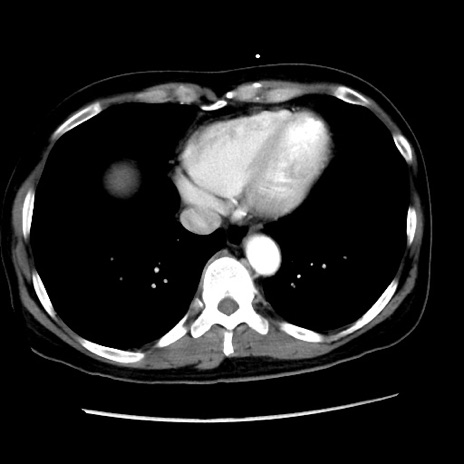

症例10(横断像)

【症例】 50歳代女性

【主訴】 腹痛

【現病歴】前日生レバーを食べた。今朝に排便あり。 昼前に突然発症の腹痛を生じ、当院救急外来を受診した。

【既往歴】 子宮筋腫にてで子宮全摘後

【身体所見】 意識清明、腹部:平坦、軟、下腹部やや左を中心に圧痛・反跳痛あり、筋性防御あり

【データ】WBC 7800、CRP 0.07